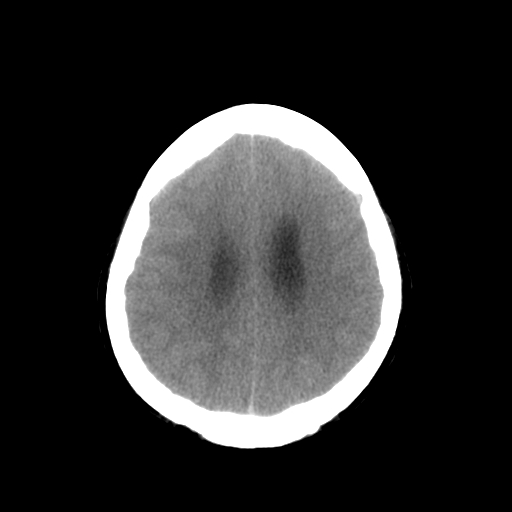

男,34岁,头痛数天。请大家看看是否有占位.

脑干、右侧桥臂及右侧小脑半球可见等低混杂密度影,环池部分闭塞,小脑上池及第四脑室受压移位、闭塞,考虑占位性病变可能性大,胶质瘤?室管膜瘤?不除外脑神经如听神经瘤及梗塞等,建议上传骨窗

疑右侧听神经瘤并梗阻性脑积水,空蝶鞍。建议行ct增强扫描检查。

右侧小脑半球占位压迫四脑室并幕上脑积水征像;建议增强或mr检查

脑干、右侧桥臂及右侧小脑半球可见等低混杂密度影。轻度脑积水。考虑右侧桥臂区域占位性病变。建议mri检查。